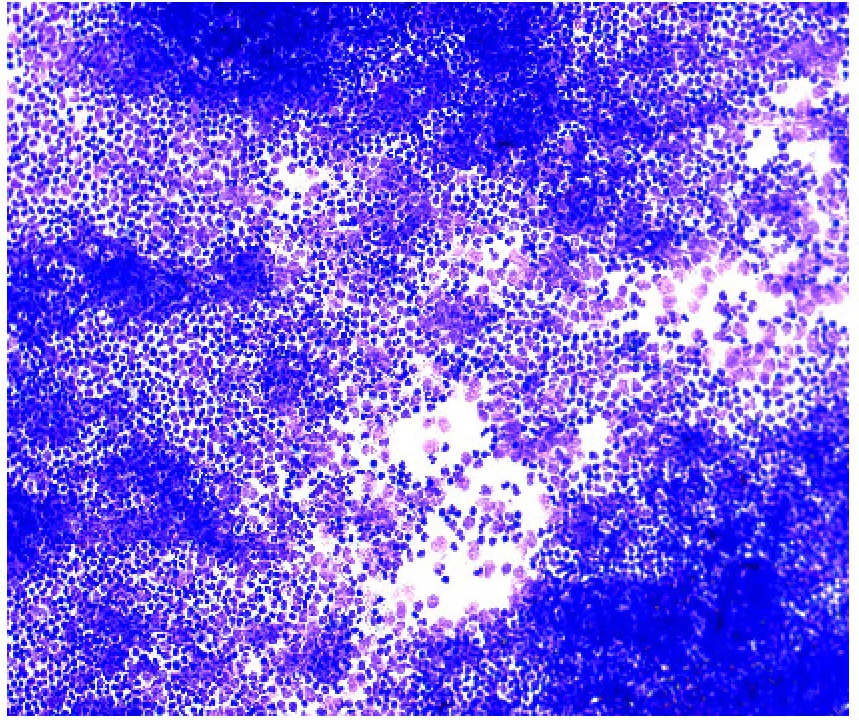

显微镜下看到的也是密密麻麻的炎性细胞!

image.png